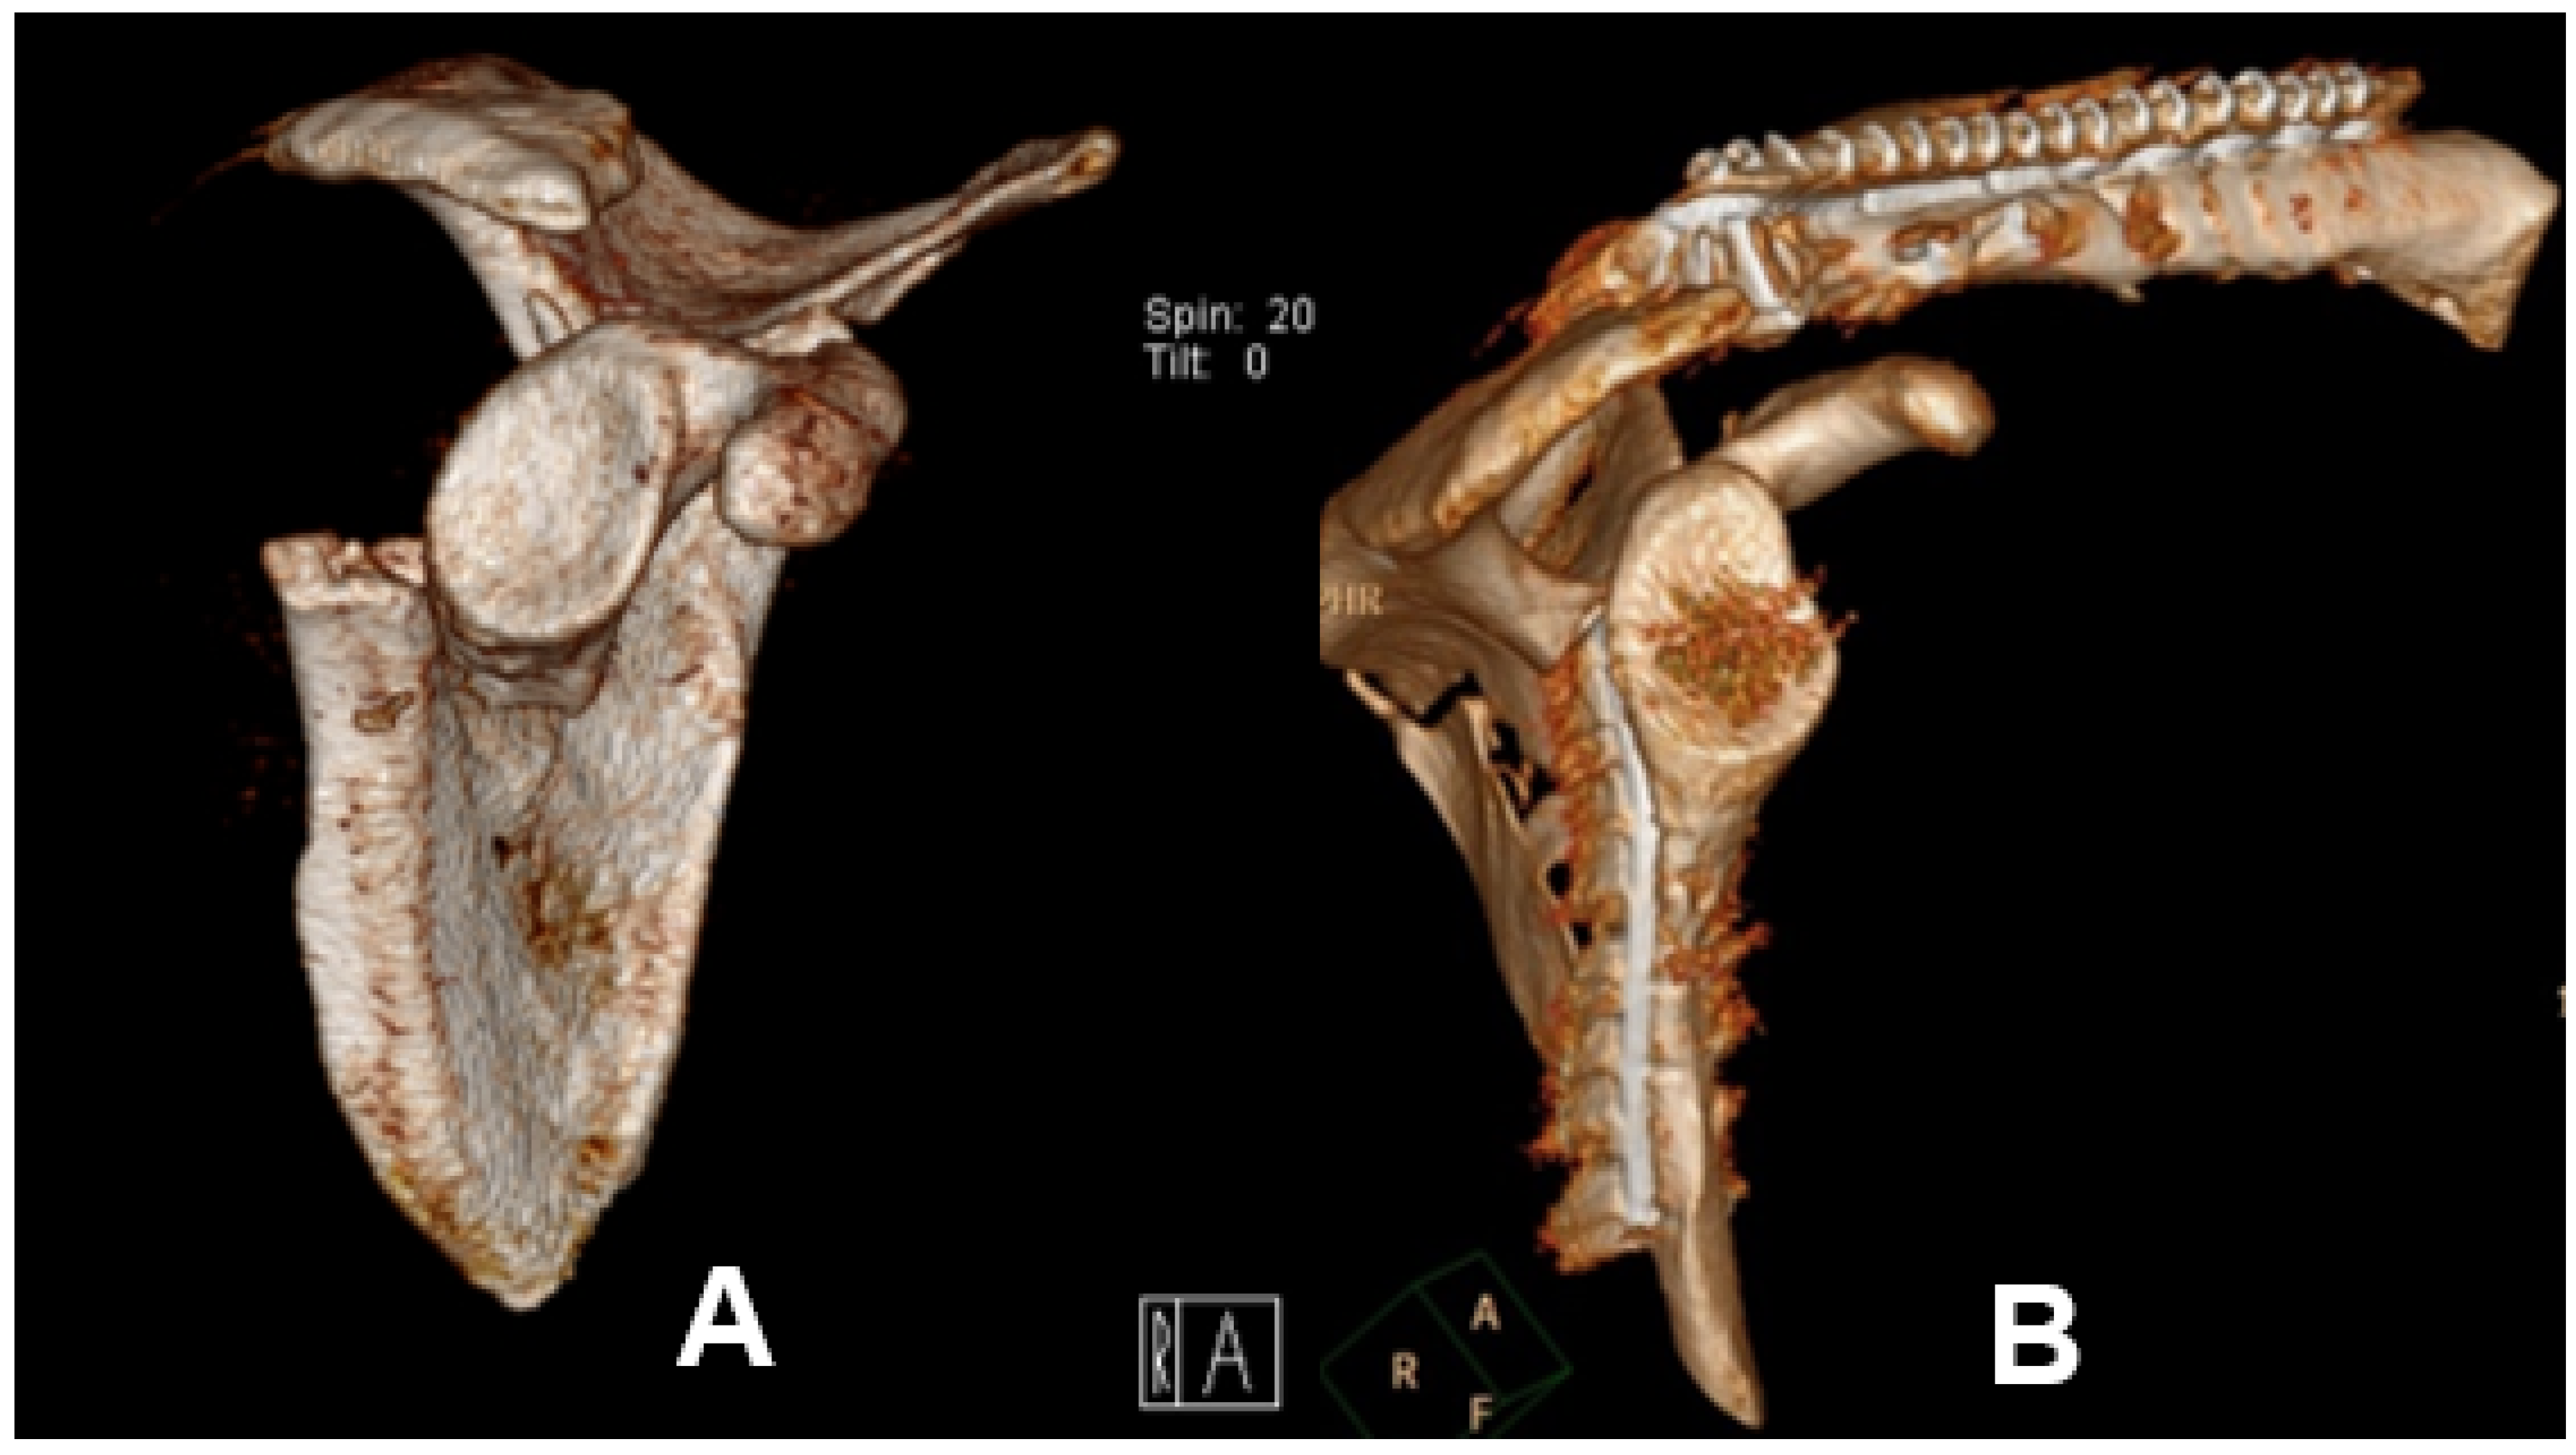

According to the indication of surgery, there were six patients (28.6%) with severe displacement of the scapula body consecutively undergoing an open reduction and internal fixation (ORIF) of the scapula body. In all patients, the Arthrex® clavicle fracture plate system was used (see Figure 3).

Figure 3. 3D reconstruction of CT imaging of displaced scapula body fracture classified according to the orthopedic trauma association as OTA 14.A3.2 (A) before Open Reduction Internal Fixation (ORIF), (B) after ORIF.